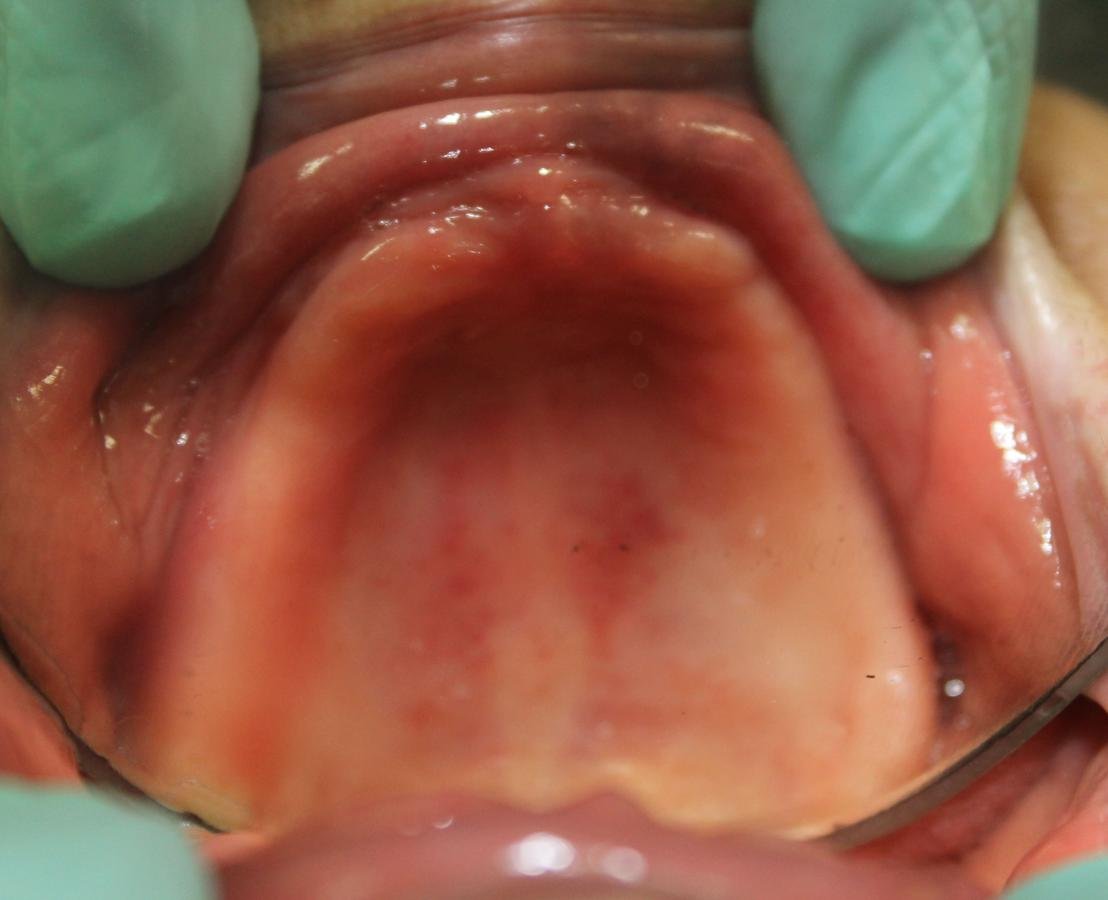

EXAMEN INTRAORAL

"Siento como si me quemara toda la boca" Paciente

7 días después

ESTOMATITIS DE CONTACTO ALÉRGICA

CAUSADA POR ACRÍLICO